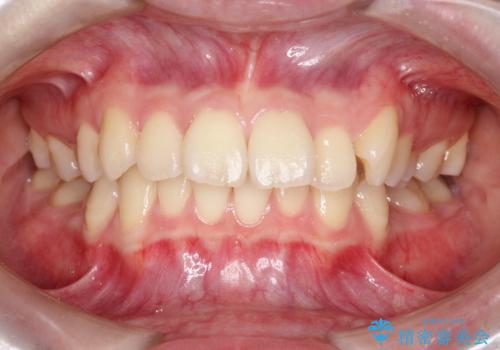

突き出た前歯を下げて理想的な横顔に。上下左右4番抜歯による審美ワイヤー矯正

担当医 河口智英